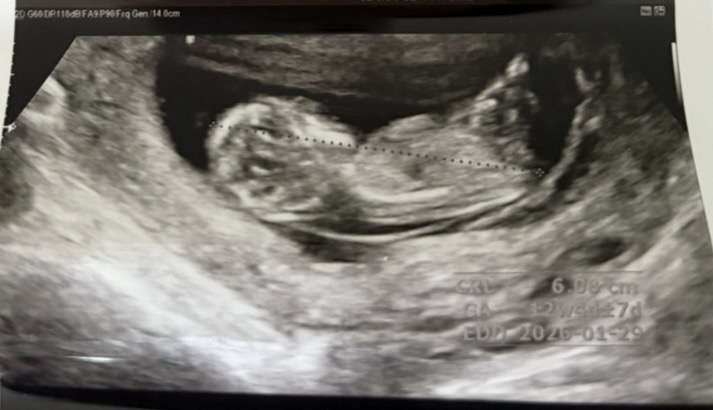

11주 6일 초음파인데 이 사진으로 각도법 볼 수 있으려나요 ㅎㅎ 성별 너무너무 궁금한데 많은 참견 부탁드려요🩵🩷

왕자님에 한표요! 다리사이에 그게보여요